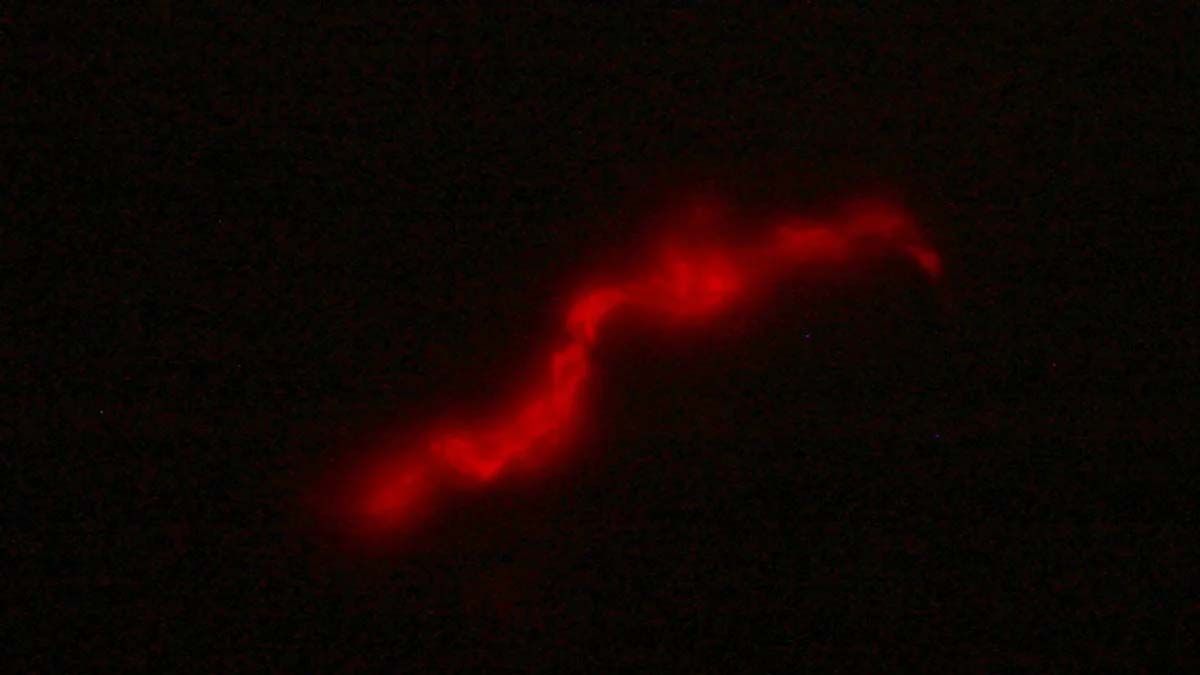

El kit está dotado de un bacteriófago, es decir de un tipo de virus que cuando entra en contacto con la bacteria de la tuberculosis, presente en la muestra de esputo del paciente, expresa una proteína fluorescente lo que permite una lectura directa mediante microscopía de fluorescencia. A futuro plantean automatizar la detección, empleando un microscopio de bajo costo y un programa que por IA pueda contabilizar bacterias fluorescentes en la muestra del paciente reduciendo los tiempos de lectura y la subjetividad del operador.